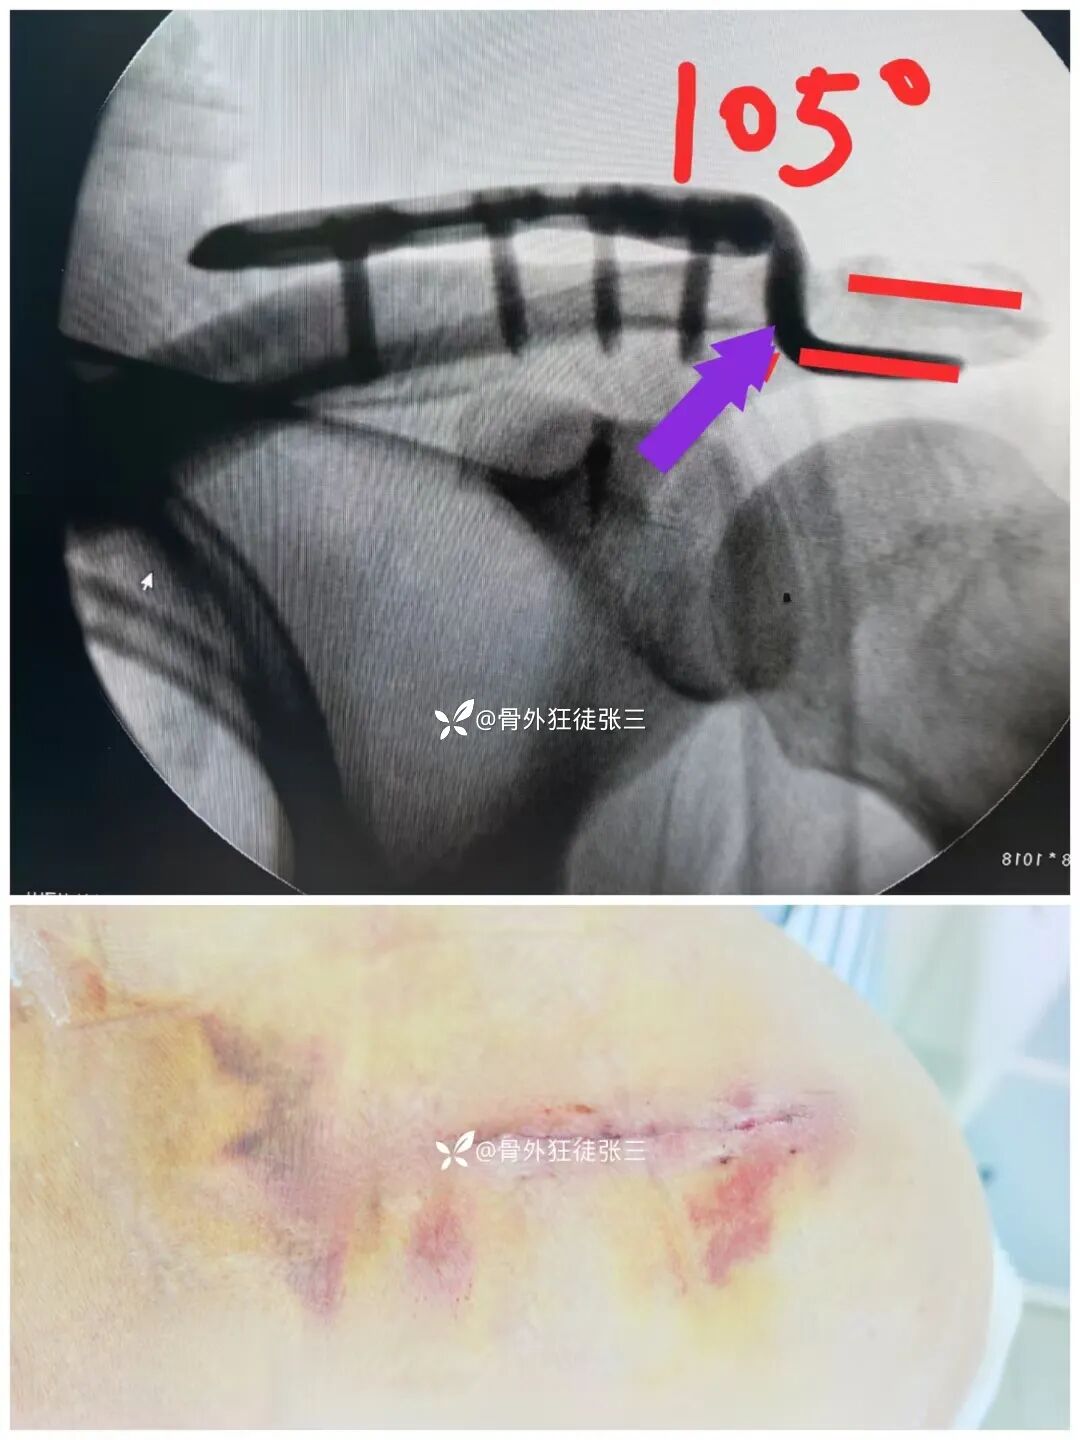

锁骨钩板使用不当术后的并发症实在太多了

肩峰撞击综合症,肩峰骨质的磨损吸收、肩峰下滑囊炎、冈上肌腱炎、近侧端因应力过大可致钢板断裂、板钉松动,甚至骨折

这些异常的摩擦均可刺激局部神经、导致疼痛的发生,从而影响患者功能的锻炼和恢复

钩板虽然需要取出

但是还是目前肩锁关节脱位最牢固的固定方法

本期主要写锁骨钩板的使用经验和如何避免并发症

如何放置和术后处理

术后外展枕

这也是我们术后严格遵守的

外展枕保护4-6周